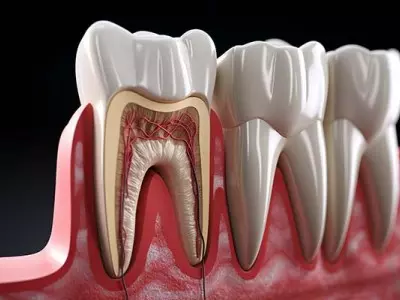

W tym wydaniu m.in: stany nagłego zagrożenia życia w gabinecie stomatologicznym, zespół zmian endo-perio, zmiany w kompetencjach higienistek i asystentek stomatologicznych, dokąd zmierza prawo i praktyka w stomatologii.